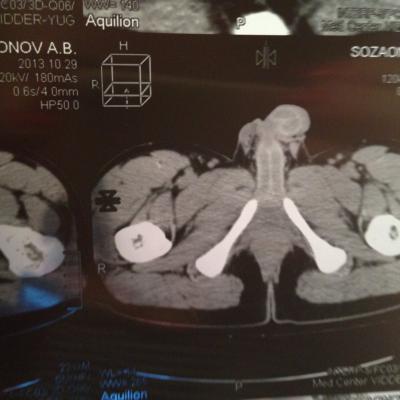

проведена МСКТ области таза!Внеорганных дополнительных патологических образований,лимфаденопатии или свободной жидкости в области таза не выявлено.

Предстательная железа-без грубой органики,еденичные микрокальцинаты.

Семенные пузырьки-конфигурация не совсем типична,примерный размер правого 26*28мм.Отмечаются признаки кистовидной трансформации и микрокальцинации обоих пузырьков.Наибольшая из кист слева достигает 9 мм.Обращает на себя внимание неравномерная кальцинация стенок крупных регионарных(текстикулярных)артерий с обоих сторон.

Костно-деструктивных изменений характерных для mts со стороны костей таза не отмечено.

Заключение:на момент исследования,КТ-данных за наличие внеорганных дополнительных патологических образований,лимфоденопатии или свободной жидкости в области таза не выявлено.КТ-признаки в пользу проявлений калькулезного везикулита с элементами кистовидной трансформации семенных пузырьков.